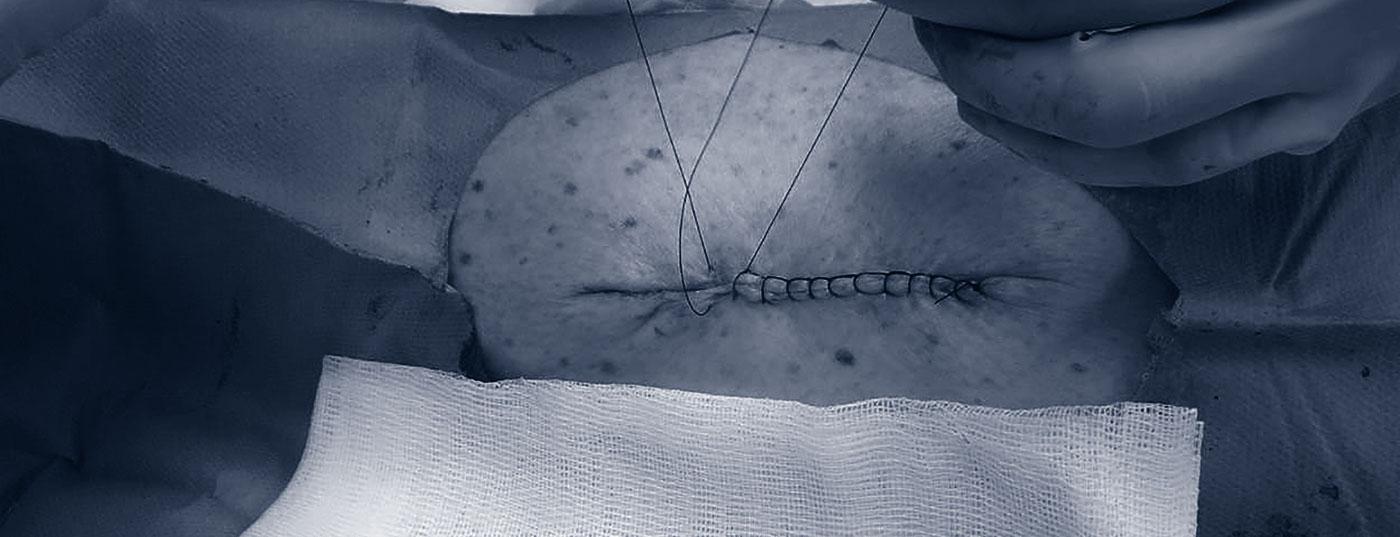

In Anbetracht der massiven Zunahme von Hautkrebs gewinnt auch die Dermatochirurgie an Bedeutung. Viele Hautkrebspatienten können mit Biopsien und Exzisionen in der Praxis diagnostiziert und behandelt werden. Neben dem Beherrschen der einfachen chirurgischen Techniken ist auch die Erfahrung mit anderen, nicht-chirurgischen Verfahren relevant. Ebenfalls wichtig sind Kenntnisse, wann eine Überweisung für aufwändigere Interventionen, wie zum Beispiel Mohs-Chirurgie, notwendig ist.